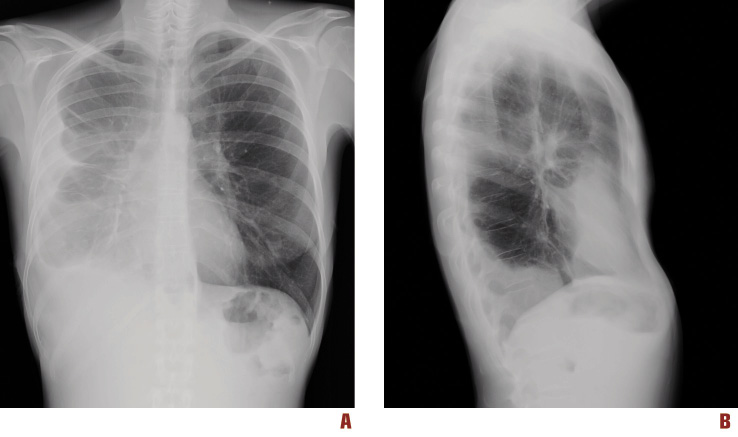

A chest x-ray after two months detected only a fibrotic area on the front surface of the right pleura (Figure 3). The general conditions of the patient improved progressively. She returned to work after two months.

Figure 3. Chest x-ray after two months from the beginning of treatment. In the frontal (A) and lateral views (B) the pleural effusion appears resolved; only a fibrotic area on the front surface of the right pleura is visible